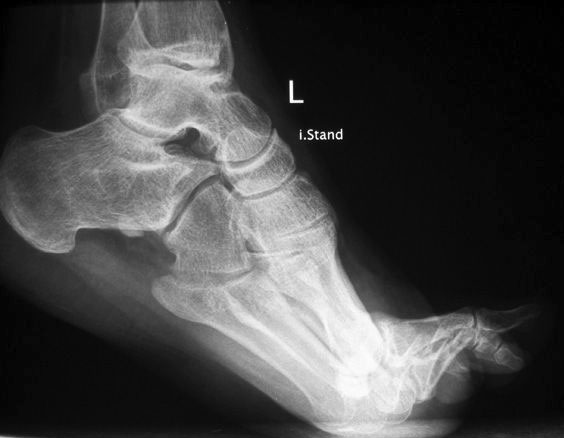

• Fuß belastet dp und seitlich (Abb. 14 und 15)

• Saltzman view (Abb. 16)

Zum Lesen der Bildbeschreibung und zur Vollansicht bitte die Bilder anklicken. Bilder: A. Simon

Typische Merkmale der Standard-dp-Röntgenaufnahme des Fußes im Stand

• Talus und Calcaneus verlaufen fast parallel

• Os naviculare ist gegenüber dem Talus nach medial gedrängt

• Metatarsalia überlappen sich basisnah

• Metatarsale I erscheint verkürzt

• Metatarsus adductus

Typische Merkmale der Standard-Seitaufnahme des Fußes im Stand

• Knöchelgabel ist außen rotiert

• Sinus tarsi ist einsehbar

• Subtalare Gelenklinie verläuft horizontal und ist breit einsehbar

• Der Abstand Malleolus medialis zum Os naviculare ist verkürzt

• Der Calcaneus erscheint verkürzt

• Der Krümmungsscheitel des Fußes ist erhöht

• Calcaneus pitch ist meist erhöht, der Rückfuß Equinus ist eher selten 12